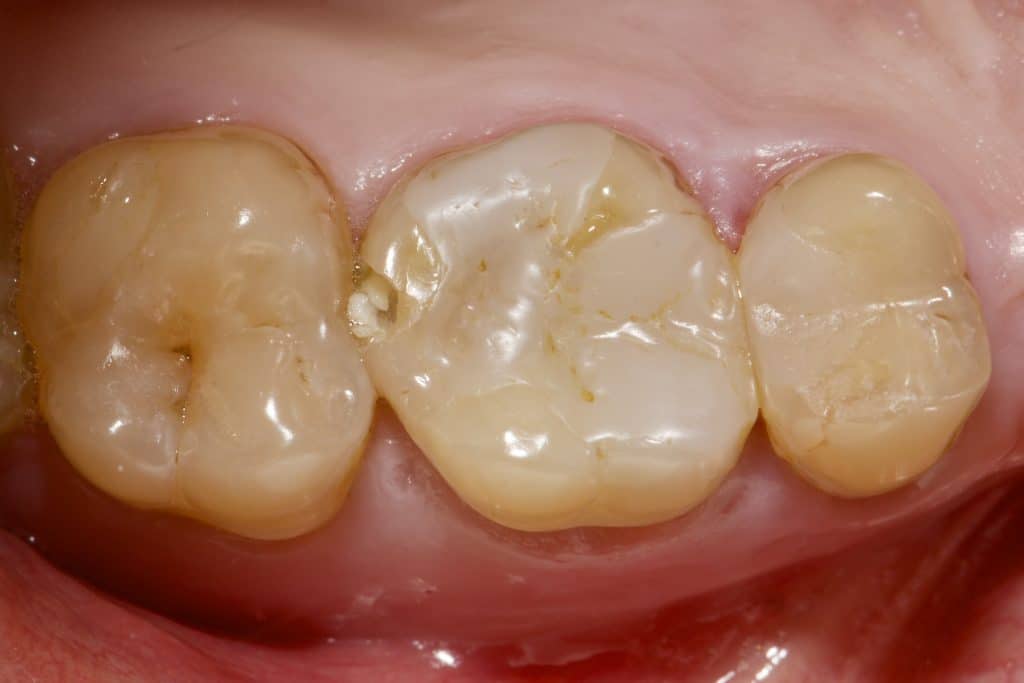

“Can a direct composite overlay function as effectively as an indirect lithium disilicate restoration? Composite restorations, once used as a long-term temporary solution for badly damaged molars, are now considered permanent. While the composite material remains the same, our understanding of its adhesive and physical properties has evolved. The procedure may be more time-consuming and require multiple stages in the same visit, depending entirely on the dentist’s skills.